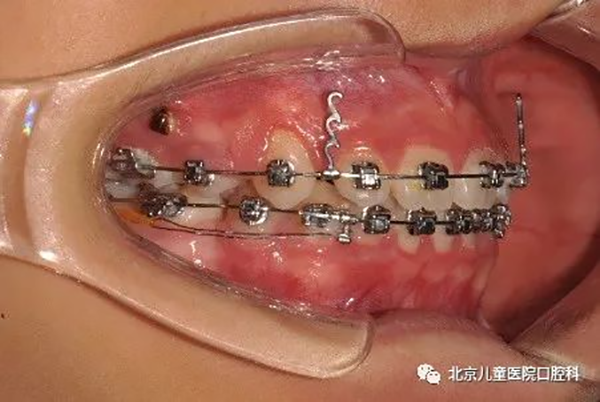

2、前牙严重前突,需要最大限度内收前牙,改善面下1/3美观。

治疗中